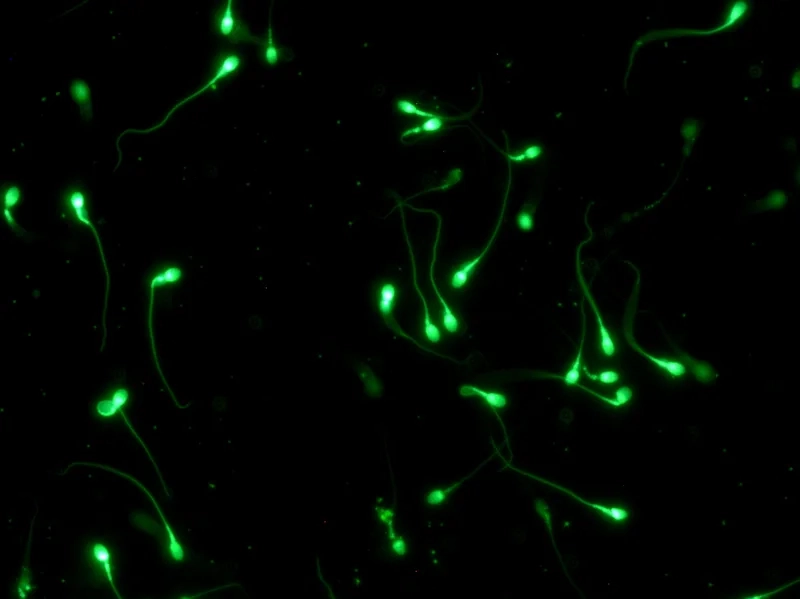

Khám phá những hình ảnh tinh trùng dưới kính hiển vi trong bộ sưu tập này sẽ cho thấy sự khác biệt rõ rệt giữa hình thái tinh trùng bình thường với tinh trùng dị dạng.

Tinh trùng dưới kính hiển vi không chỉ là một hình ảnh sinh học cơ bản mà còn là yếu tố quyết định sức khỏe sinh sản. Việc tìm hiểu cấu tạo và chức năng của tinh trùng giúp chúng ta hiểu rõ hơn về khả năng thụ thai.